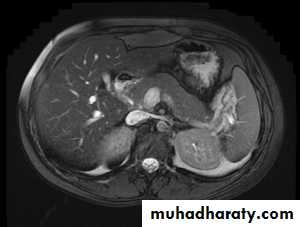

MRI